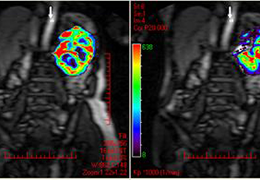

View X-Ray CT & MRI Scans Fast and Easily

Designed for surgeons, Pro Surgical 3D makes it easy to view patient scans quickly. Pro Surgical 3D facilitates the optimal 3D treatment and assessment workflows based on X-ray CT and MRI scans – and best of all, it’s FREE!

Performs 3D reconstruction and volume rendering.

Multi-planar slicing.